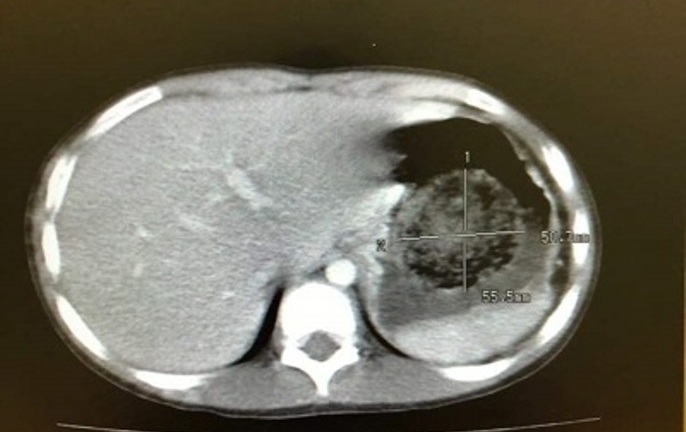

Sau khi kiểm tra, các bác sĩ nhận thấy bụng bệnh nhân chướng nhiều, tuần hoàn bàng hệ dương tính, dịch ổ bụng mức độ nhiều. Vòng bụng của bệnh nhân có số đó 120cm, tương đương với người mang thai 9 tháng. Cụ bà được thực hiện các xét nghiệm lâm sàng. Kết quả cho thấy CT ổ bụng có nang buồng trứng trái kích thước 26x19x15cm chèn ép các tạng trong ổ bụng, có nhiều ngăn, nhiều vách mỏng, không có nụ sùi, nhiều dịch tự do trong ổ bụng.